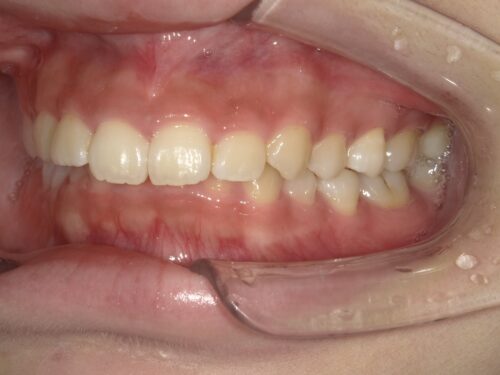

治療中・左側の写真

治療中・右側の写真

左右からも確認すると、上の前歯が少しずつ後方に下がってきているのが見えます。